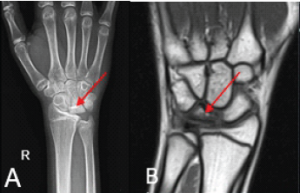

Standard AP and lateral radiographs of the left elbow (Fig. 1) revealed an olecranon fracture with a radial head fracture, which still did not explain the gross instability in both planes. Hence, a CT scan (Fig. 2) was done, which revealed a fracture of the coronoid (Regan and Morrey Type II, O’Driscoll Type II) along with elbow subluxation [6,7]. Ideally, an MRI should have been done to see the status of the ligaments, but we were unable to get one due to some logistic concerns at our institute. As the injury was already 3 weeks old and did not want to delay further, we decided to go ahead with the surgery, and had any ligamentous instability been found after bony fixations during the surgery, we would have repaired that by suture anchors. All of this was explained to the patient and then only he was posted for surgery.